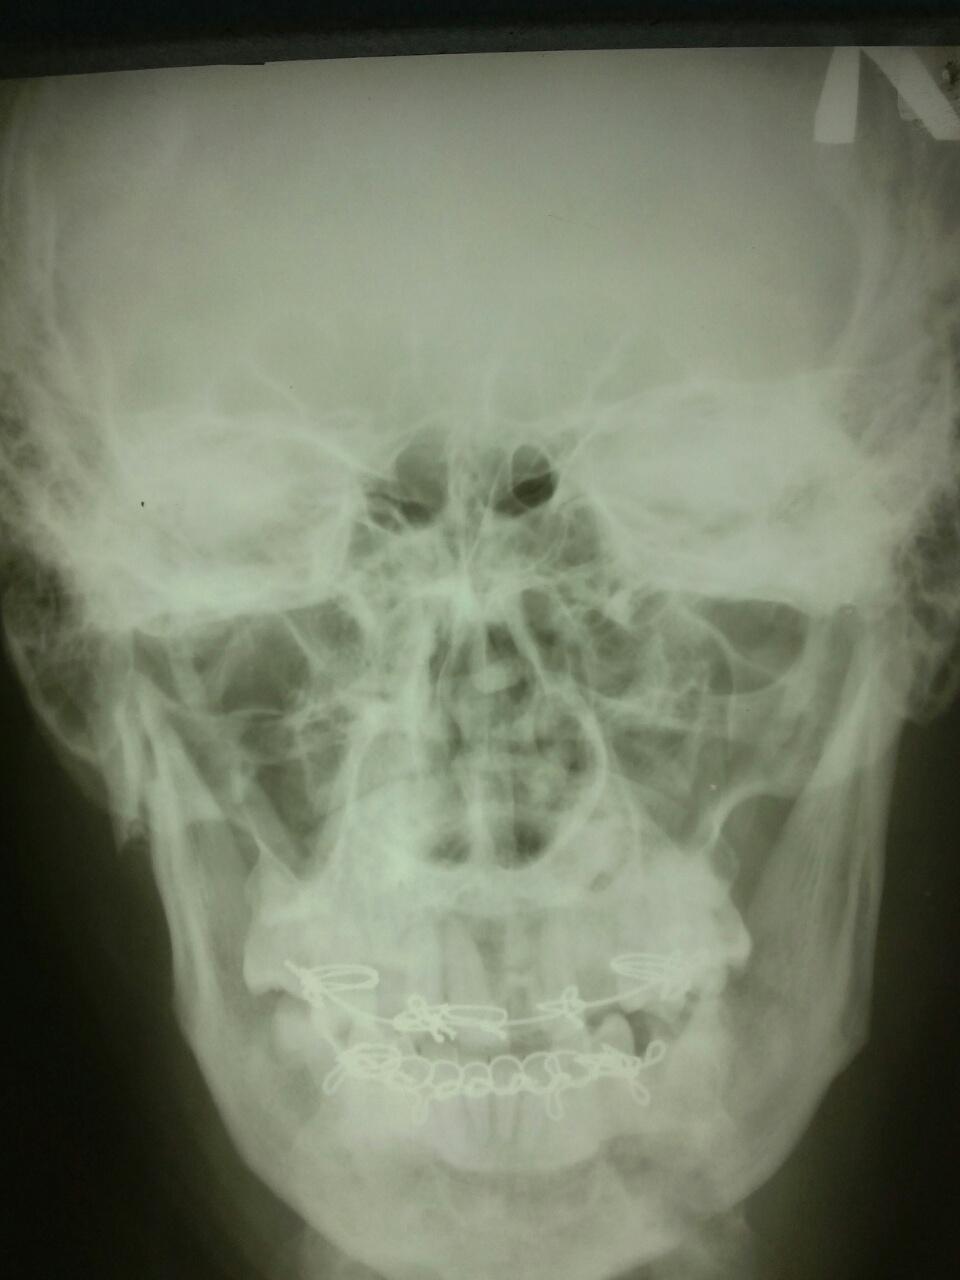

Привет пикабушники, вот решил тоже начать публиковать записи, но с чего начать так и не додумался кроме как показать вам случай с работы. Привезли как то к нам в отделение гопника со сломанной челюстью. На первой картинке день побоев, на второй уже спустя 14 дней (видно как скрепляли и выравнивали зубы) . Вот так вот выглядит разбитый нос и сломанная челюсть в двух местах. Надеюсь мой первый пост вам понравился)

Фоткал и описывал я, тег Моё